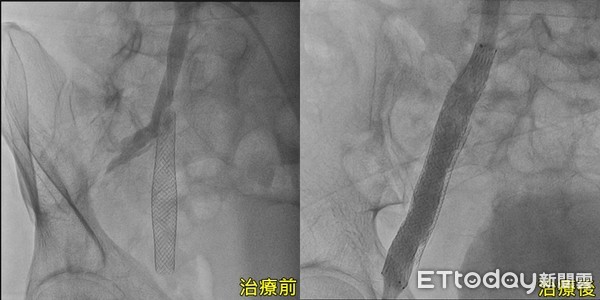

南投59歲王先生因終日久坐辦公,導致右腿飽受腫脹、膚色暗沉、皮膚潰爛所苦,甚至行走困難,雖曾就醫確診為下肢深層靜脈栓塞,五年前置放支架後狀況有改善,但因未定期服用抗凝血劑,以致於血管內支架再度狹窄,右腿更腫如「豬肝色」所幸緊急重新打通並置放第二支支架,術後一週表皮傷口癒合,讓他恢復健康人生。

劉殷佐也強調,該患者原本患有心血管疾病,加上工作關係需長期保持固定坐姿,屬下肢深層靜脈曲張的高危險群,雖先前因同樣的原因放置支架,但因靜脈支架原本就相對容易狹窄,加上沒有遵照醫囑服用抗凝血劑,才會導致症狀始終無法有效控制,但透過重新打通血管,並再放一支支架,患者隔天就能下床行走,一週後傷口順利癒合,徹底解決長久以來的困擾。